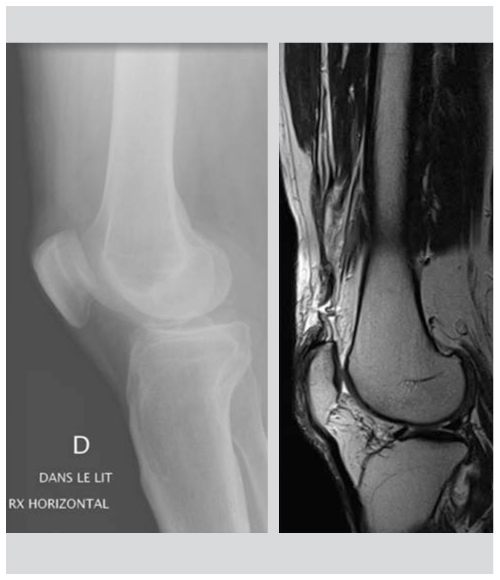

Rupture De L Appareil Extenseur Du Genou Medicinus

Ruptures De L Appareil Extenseur Du Genou Revue Medicale Suisse